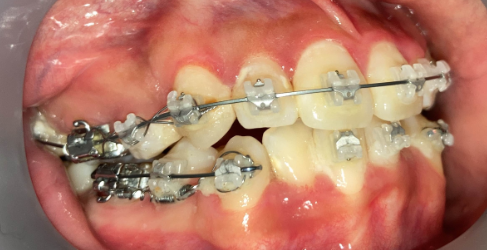

抜歯矯正1年後の口腔内|奈良の矯正歯科

治療1年後

他院で非抜歯矯正を受け、歯並びは改善したものの、口元の突出感が残ったまま治療が終了。当院で精密検査を行った結果、上下4本の抜歯によるリカバリー治療が必要と判断しました。